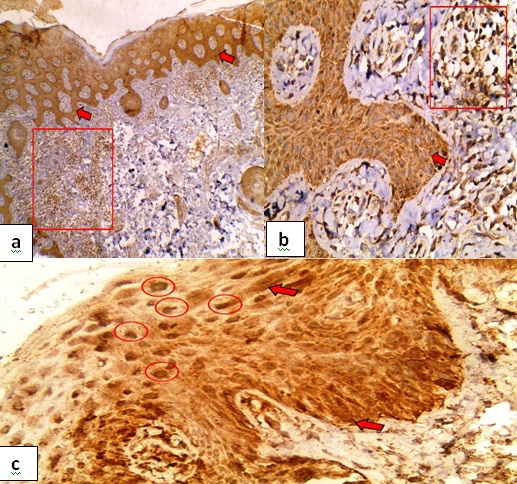

Psoriasis: Caspase-3 was expressed in 85% of the cases. Diffuse, strong and nucleo-cytoplasmic expression was noticed in 82.4%, 70.6% and 88.2% cases respectively. H score ranged from 70-240. Ninety five percent of cases expressed caspase-3 in the inflammatory infiltrates while none of the adnexa expressed caspase-3 [Table/Fig-2].

Caspase-3 in psoriasis- a) diffuse nucleo-cytoplasmic expression in the overlying epidermis (red arrows), caspase-3 was also expressed in the sub-epithelial inflammatory infiltrate (red box) (Immunoperoxidase, 4X); b) Higher power of the previous slide exhibiting diffuse cytoplasmic expression in the overlying epidermis (red arrow) and its expression in the subepithelial inflammatory infiltrate (red box). (Immunoperoxidase, 40X); c) Diffuse cytoplasmic expression in the overlying epidermis (red arrow) and its expression in the nucleus (red circle) (Immunoperoxidase, 40X).